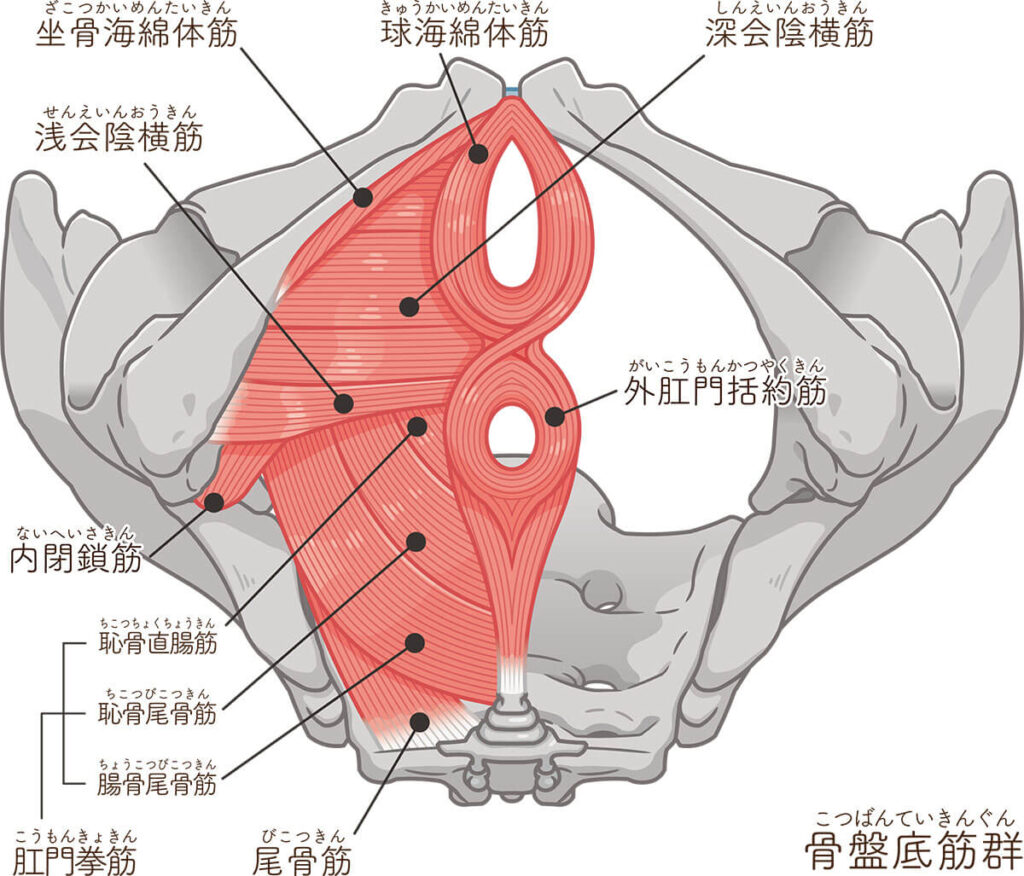

骨盤底筋群とは?

骨盤底筋群(こつばんていきんぐん)とは、骨盤の底にあるハンモック状の筋肉の集合体で、複数の筋肉や腱でできています。恥骨や坐骨、尾骨などの骨を支えてます。

腹圧を調整する

骨盤底筋には、腹圧を一定に調整する役割もあります。腹圧とは、おなかの中の空間を保つ圧力のこと。骨盤底筋は、肺呼吸に関わる横隔膜、おなかの腹横筋、背中の多裂筋とともに腹圧を調整しており、体幹を構成するインナーマッスルとも呼ばれます。

腹圧が低下して体幹が不安定になり、姿勢が悪くなったり、内臓の働きが悪くなったりすることがあります。